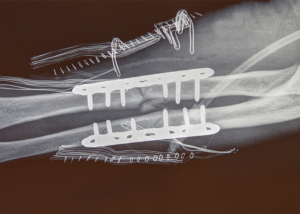

Sarah was walking to her car in a parking lot. An elderly driver began to back up his car and pinned her between his car and her car, thereby severely fracturing her arm. The fracture required open reduction internal fixation surgery whereby she had surgical hardware installed inside of her arm.